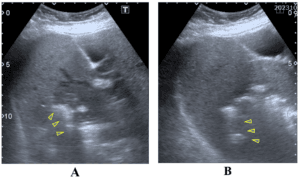

A 19-year-old male presented with a long-standing history of discharge from two openings at the upper part of the natal cleft. He had multiple pits at the midline. POCUS showed the sinus tract extending from the midline up to the secondary openings. A modified Lord Millar excision was done (Figure 2).

Figure 2. Complex pilonidal Sinus. A) Multiple midline pits and two secondary opening cranially. B) Post modified Lord Millar excision. C) Ultrasonographic view at the midline of natal cleft showing multiple pits (arrowheads) and the pilonidal sinus with hair within (arrow). No craniocaudal extension. D) Ultrasonographic view at the upper part of the natal cleft showing the cranial extension of the pilonidal sinus towards the secondary openings.